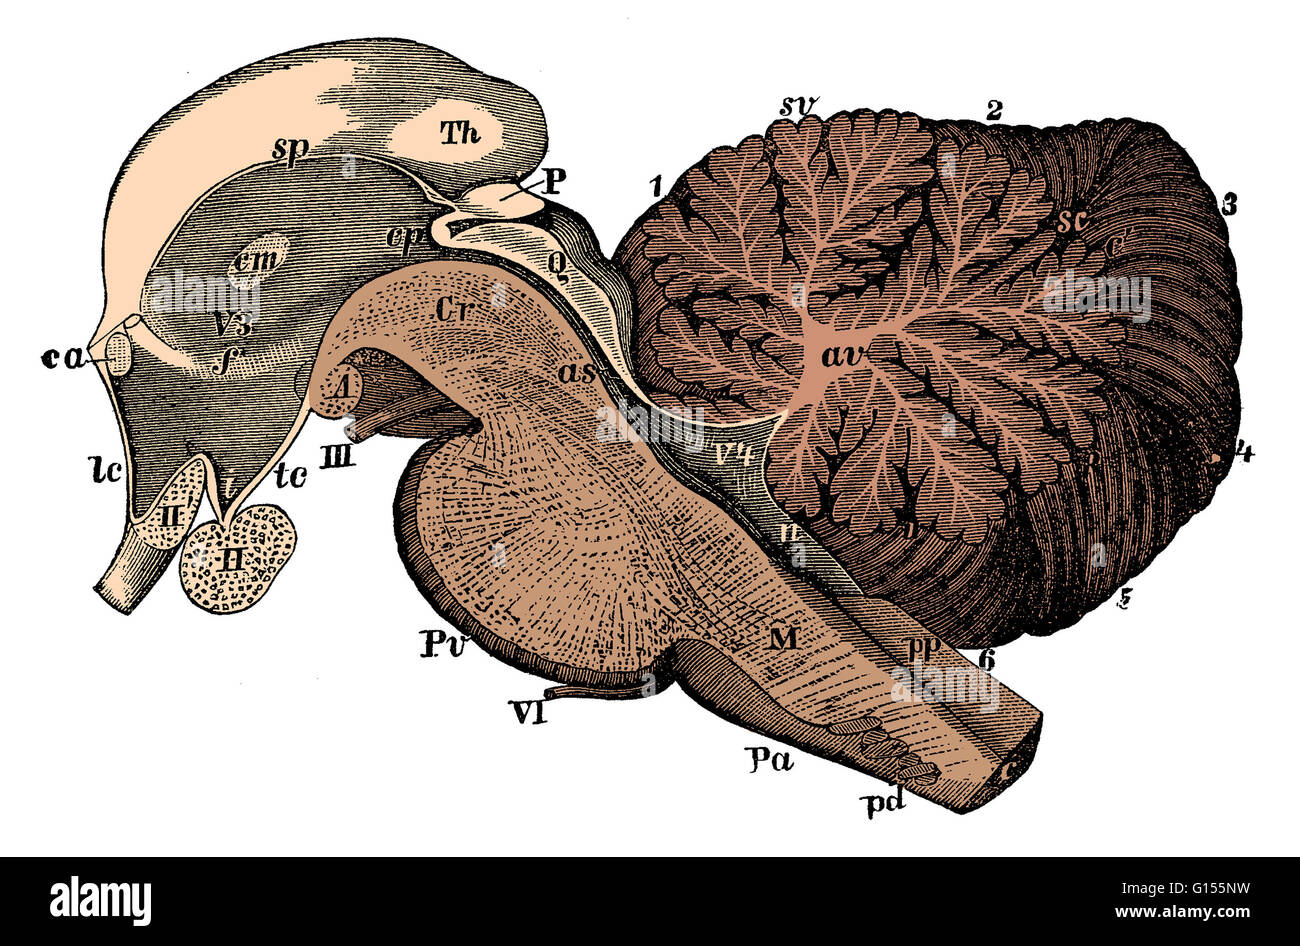

RMG155NT–Illustration einer sagittalen Abschnitt der dritten und vierten Ventrikel des Gehirns. Die Ventrikel enthalten Liquor cerebrospinalis, die das Gehirn dämpft. Dies ist eine historische Darstellung aus den 1890er Jahren.

RMG155NW–Verbesserte Darstellung der sagittalen Abschnitt der dritten und vierten Ventrikel des Gehirns Farbe. Die Ventrikel enthalten Liquor cerebrospinalis, die das Gehirn dämpft. Dies ist eine historische Darstellung aus den 1890er Jahren. (Abb. BS4911)